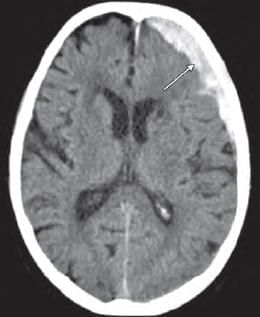

Mention the arterial supply of the marked structure: (INI-CET May 2022)

Detailed Solution for Test: Anatomy - 3 - Question 2

The arrow mark indicates the rostrum section of the corpus callosum, which is supplied by the anterior cerebral artery and the anterior communicating artery. The blood supply to the corpus callosum comes from:

• A branch of the anterior communicating artery (the median callosal or subcallosal artery)

• The pericallosal artery (the distal portion of the anterior cerebral artery)

• The posterior pericallosal artery (typically a branch of the posterior cerebral artery)

Additional notes:

• The splenium of the corpus callosum is supplied by the posterior pericallosal artery (a branch of the posterior cerebral artery).

• The middle cerebral artery supplies the lateral aspect of the corpus callosum.

It is important to note that the rostrum of the corpus callosum (commissural fibres) connects the orbito-frontal cortex of both sides for inter-hemispheric transfer of information.